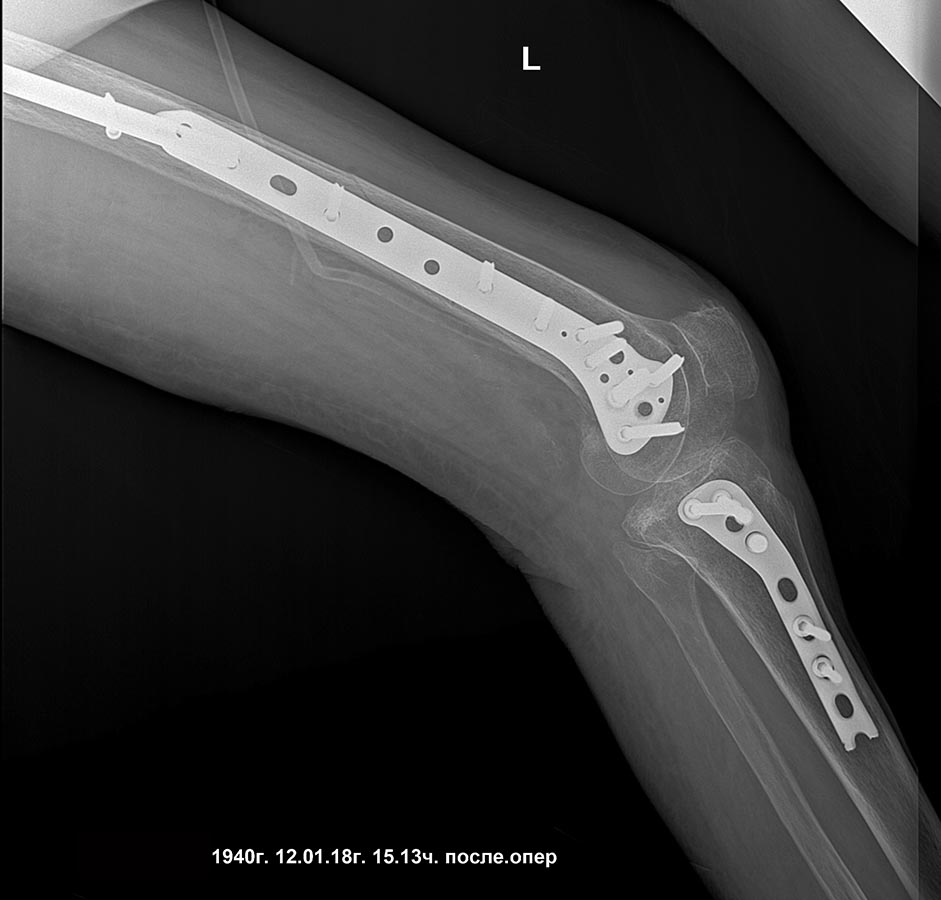

[Ortho] Сросшийся чрезвертельный и перелом н\3 бедра

бедро